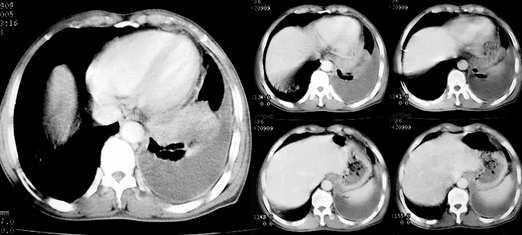

以下是引用jiajie在2005-11-6 22:07:00的发言:[br]1)左肺下叶阻塞性肺炎,胸腔积液,中心型肺癌可能大,建议纤支镜。[br]2)结合30年打石史,双肺弥漫性小结节考虑矽肺。

以下是引用sdqzwyx在2005-11-7 19:59:00的发言:[br]双肺弥漫大小不等的粟粒状结节影;肺纹理走行失去自然,粗细不均,边缘不规则,小叶间隔增厚;左上肺示不规则形致密影,从斑块边缘向周围伸出长短不一的致密索条影,临近的血管、支气管和叶间胸膜等结构受牵拉移位;左下肺示不规则团块状影,其内示空洞,洞内壁尚光整,左侧胸腔积液。右肺下叶背段亦示部分病灶融合。双肺可见局限性肺气肿。[br]诊断:结合病史符合三期矽肺表现(少数矽肺纤维斑块内可以形成空洞,一般认为是斑块中央感染引起坏死所致)但尘肺病人易合并肺结核,诊断可为三期+tb。所以此病人应进一步检查是否合并结核。